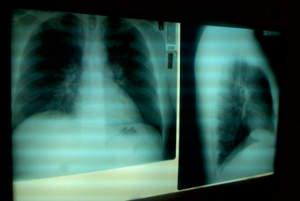

Виды пневмоний. Помимо известных многим односторонней (если поражено одно лёгкое) и двусторонней (если пострадали оба) пневмонии, специалисты выделяют целый ряд разнообразных подгрупп заболевания:

Как видно из приведённой классификации, основанием для неё выступает степень поражения лёгкого и близлежащих тканей. Острые пневмонии издавна разделяли на две основные группы: крупозную (при которой воспалительным процессом поражается целая доля легкого) и очаговую.